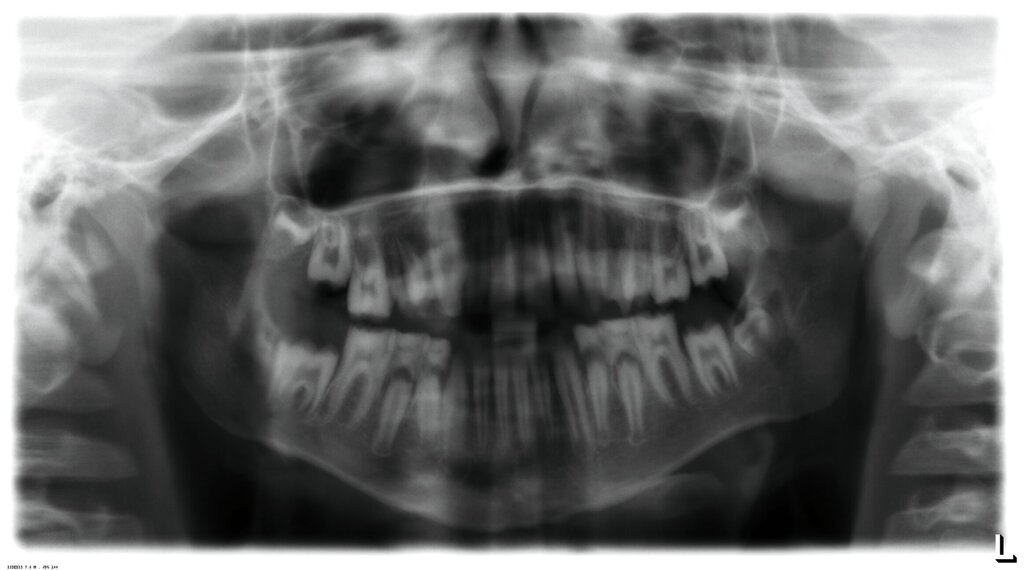

Klinisch zeigte sich ein kariöses Wechselgebiss mit generalisierten Verfärbungen und rauer Schmelzoberfläche. Mehrere Milch- und bleibende Zähne wiesen aktive kariöse Läsionen auf. Zahn 64 war zusätzlich druckdolent und gelockert, mit einer vestibulären Schwellung der Gingiva. Zudem bestanden eine Mittellinienabweichung, ein Overbite von vier Millimetern und ein Overjet von elf Millimetern (Abbildung 1). Extraoral fiel ein fliehendes Kinn mit inkomplettem Lippenschluss und hyperaktivem Musculus mentalis auf. Röntgenologisch waren alle Zähne angelegt, der Zahnschmelz zeigte jedoch eine reduzierte Opazität (Abbildung 2). Eine genetische Abklärung wurde von den Erziehungsberechtigten aus ethischen Gründen abgelehnt.